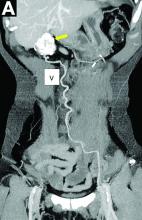

A laparoscopic resection of this mass was performed because of the risk of spontaneous hemorrhage linked to the dense tumoral vasculature and the lack of formal histologic diagnosis. During the procedure, the surgeon observed a cystic mass attached to the ligamentum teres between the liver and the umbilicus. At pathologic examination (Figure B), a well-circumscribed largely cystic mass, with a fibrous and calcified shell and hemorrhagic modifications (arrow) was observed.